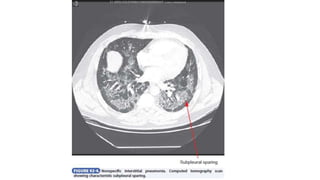

• Nonspecific Interstitial Pneumonia

Diagnosis

• Chest radiographs show bilateral patchy pulmonary infiltrates with a

• HRCT reveals a predominant ground-glass pattern of attenuation,

usually bilateral and often associated with subpleural reticulation,

• In cellular nonspecific interstitial pneumonia, HRCT shows ground-

• In contrast, fibrotic nonspecific interstitial pneumonia has a bilateral